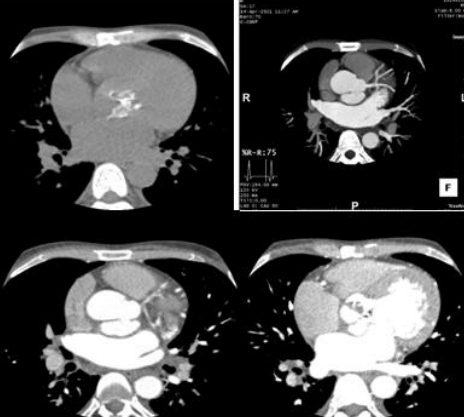

Unrupted Sinus Of Valsalva Aneurysm From Left Coronary Sinus Secondary To Brucella Endocarditis

Unruptured sinus of valsalva aneurysm (SVA) is a rare cardiac condition occurring in the general population, with potential for grave complications. Unruptured sinus of valsalva aneurysms because of Brucella endocarditis is rare , it arising from left coronary sinus is very rare. Most of the cases earlier were diagnosed by echocardiography and also by conventional angiography. But with the availability of advanced imaging mo1dalities like 128 slice cardiac CT and MR modalities, this condition can be accurately assessed noninvasively. We report a case of 40 year old male patient presenting with pyrexia of unknown origin .clinical examination revealed early diastolic murmur and ejection systolic murmur.